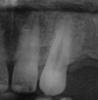

Прошу квалифицированного совета. Ситуация такая – заболел верхний клык (13), появился на десне отек. Пошел к стоматологу. Сделали панорамный снимок (фрагмент «13 до вскрытия» выкладываю). При осмотре был обнаружен кариес под десной, стали сверлить, но после вскрытия врач сказал, что необходимо удалить нерв, что и было сделано, после этого был сделан прицельный снимок, после чего мне было сказано, что зуб сохранить нельзя, что там какая-то трещина, что он как яичная скорлупа в общем только удаление и имплантация. После этого была поставлена временная пломба и канал оставлен не пломбированным. Удалять его мне совсем не хочется, т.к 14 тоже нет, а 12 отсутствуют от рождения. Чтобы определиться решил сходить на консультацию в другую клинику. После осмотра врач сделал прицельный снимок («13 после вскрытия») и выслушав всю эту историю, сказала, что не видит ни каких особых патологий, но сама браться за этот зуб не будет, объясняя тем, что с того места, где стоит пломба невозможно прочистить канал, и что при вскрытии может что-то обнаружиться, возможно даже врачебная ошибка, поэтому возможно мне и было предложено удаление с последующей имплантацией. Посоветуйте есть ли шансы вылечить и сохранить этот зуб, т. к. он побаливает и не проходит отек десны.

надо таки вскрывать зуб и смотреть есть ли трещина. Учитывая отек на десне и глубину кариозной полости, можно предположить, что зуб не спасти уже. Но одного снимка недостаточно для того, чтобы это утверждать.